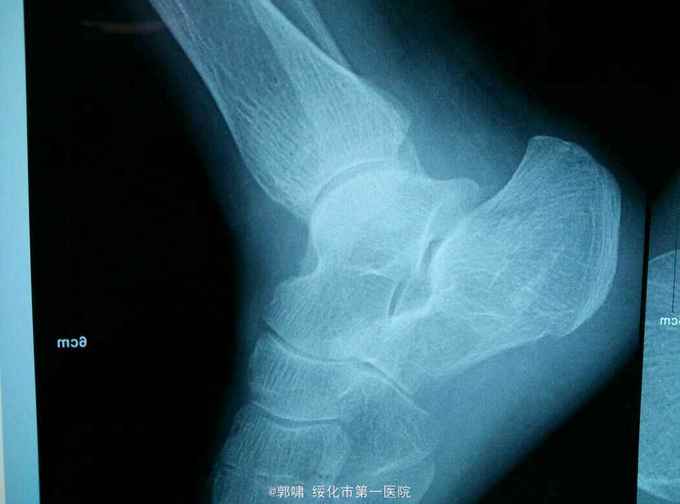

患者老年男性。76岁。自三米高处坠地。右侧跟骨肿胀痛,畸形,活动受限一小时。收入院。病人一小时前不慎自三米高处跌下,当即右足跟局部肿胀,疼痛,畸形。不能行走。立即来诊,门诊拍片示。右侧跟骨粉碎性骨折。收入院。

右侧足跟局部肿胀。足弓消失。局部皮下淤血。压痛。活动受限。不能行走。拍片示。右侧跟骨粉碎性骨折。

诊断。右跟骨粉碎性骨折。病人入院后常规检查。急诊腰麻下闭合复位。横向挤压恢复跟骨横径。克氏针撬拨恢复跟骨贝雷氏角。恢复跟骨关节面平整。沿跟骨长轴交叉传入细克氏针。拧入空心钉。